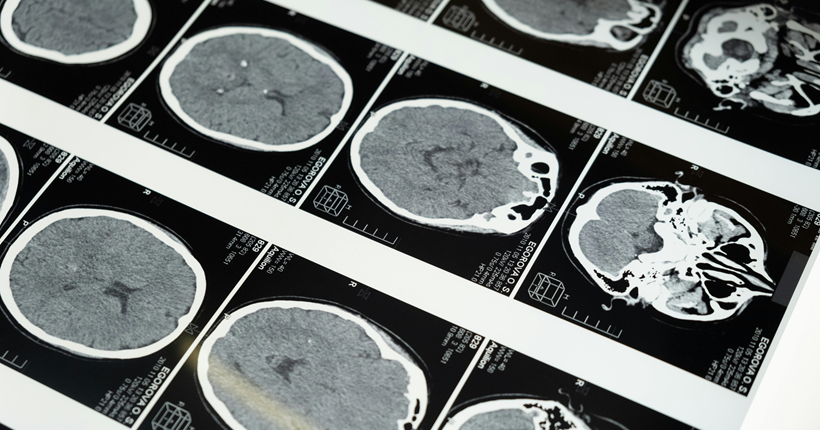

La importancia del diagnóstico precoz en el ámbito de las demencias

Desafíos para el diagnóstico precoz

A pesar de sus beneficios, el diagnóstico temprano enfrenta retos, como:

- Reconocer los primeros síntomas, que a menudo son sutiles y se confunden con el envejecimiento normal.

- Estigmas sociales y falta de conocimiento, que retrasan la búsqueda de ayuda.

- Acceso limitado a especialistas en algunas regiones, lo que dificulta una evaluación adecuada.